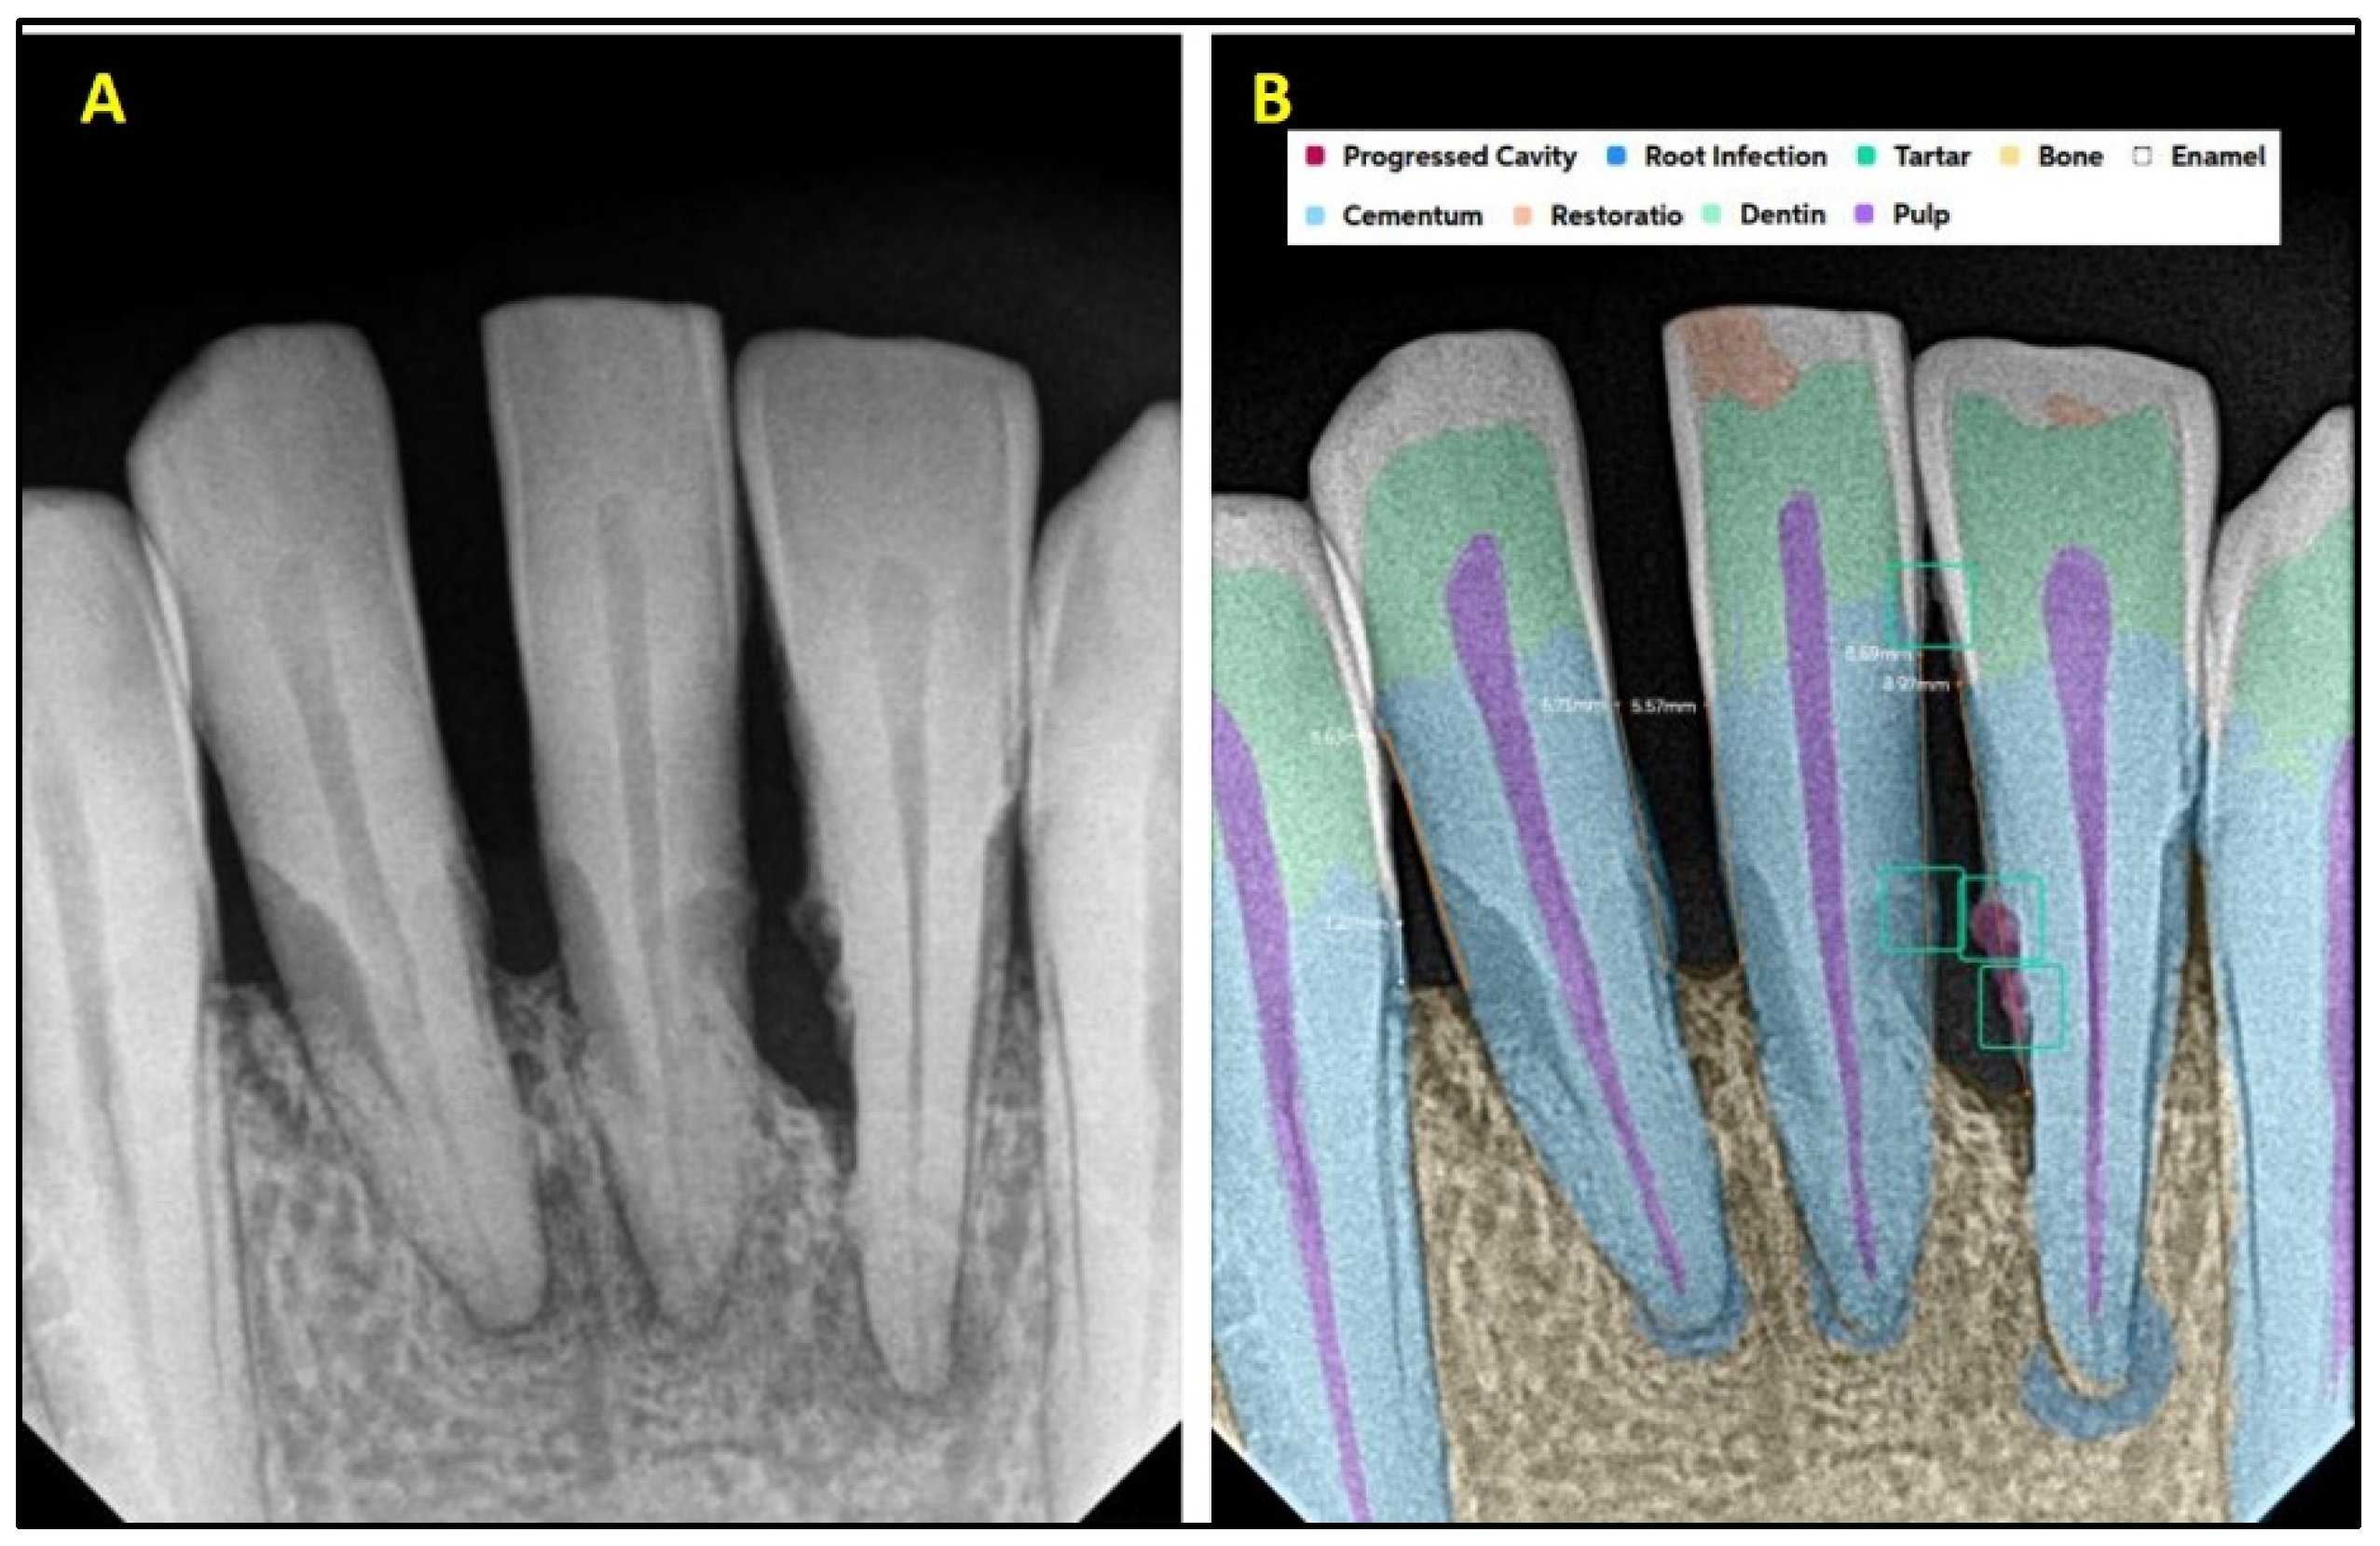

2.2. AI Software Architecture